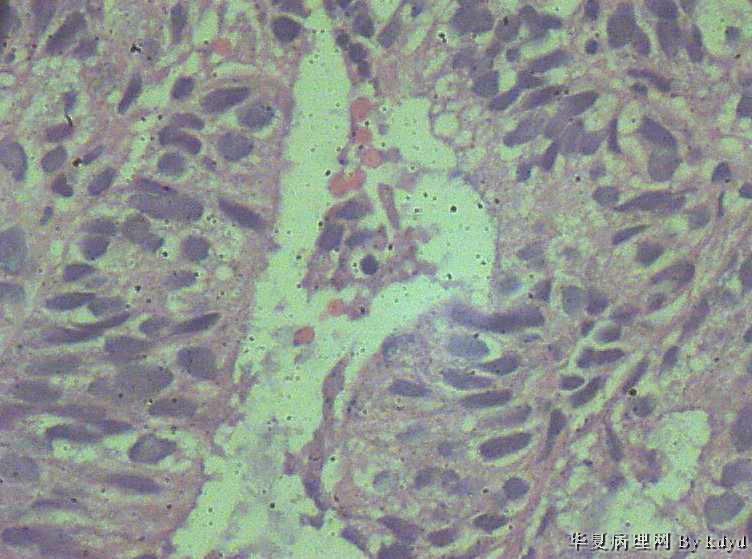

51岁,停经一年后,阴道流血。行宫腔诊刮。

疑问:1。腺体呈复杂性增生伴不典型增生?

2。腺体有分泌反应,有些腺体看上去又像是宫颈的腺体(手术医生说是宫腔取的)?

复杂性增生伴中-重度不典型增生

腺体密集,有背靠背、共壁,有乳头状结构,有核异性性,有病理核分裂:

子宫内膜中-重度不典型增生,癌变不能排除

报了个 复杂性增生伴轻-中度不典型增生。 以跟医生交代了一下,叫病人最好 进一步检查 。

宫内膜间质消失,子宫内膜癌

宫内膜样癌(高分化)。组织腺体拥挤、背靠背、血管纤维轴心乳头状,间质细胞消失代之纤维。

子宫内膜重度不典型增生,癌变。

腺癌,内膜和宫颈的很难区分,可结合免疫组化,ER\PR,上色就应该是内膜来源,不上色就是宫颈了